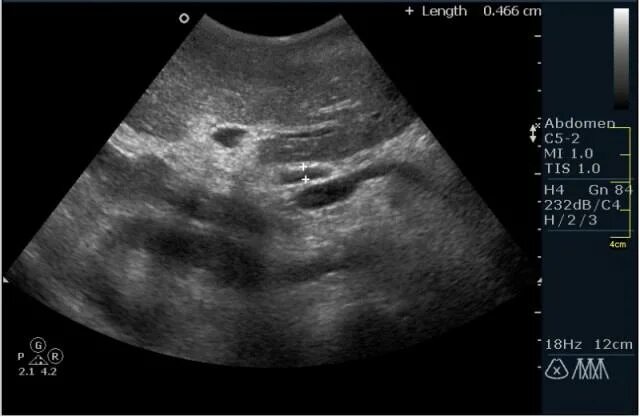

Перекрут придатков матки